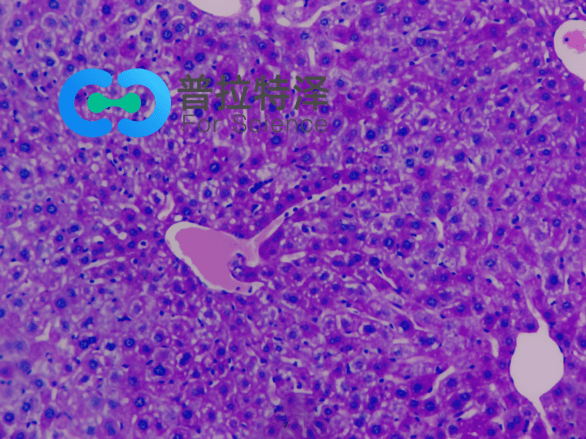

PAS染色法,全稱為過碘酸-雪夫染色法(Periodic Acid-Schiff stain)。在組織學(xué)上,主要用來檢測組織中的糖類。它利用過碘酸將糖類相鄰的兩個(gè)碳上的羥基氧化成醛基,再與Schiff試劑中的無色品紅結(jié)合,形成紅色物質(zhì),從而顯示糖原和其他多糖物質(zhì)在細(xì)胞內(nèi)的分布。

進(jìn)行PAS染色實(shí)驗(yàn)所需的主要材料包括:

→實(shí)驗(yàn)切片:通常為石蠟切片或冰凍切片,用于觀察組織中的糖類分布。

→高碘酸溶液:用于將糖類氧化成醛基,是PAS染色中的關(guān)鍵試劑。

→Schiff試劑:含有無色品紅的溶液,能與醛基結(jié)合形成紅色物質(zhì),是顯示糖原的重要步驟。

→蘇木素染液:用于細(xì)胞核的染色,以便更好地觀察糖原在細(xì)胞中的定位。